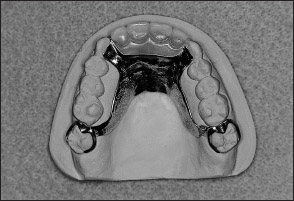

Traditionally, fixed partial dentures have been attached to abutments using dental cements, while removable partial dentures have been attached to abutments by other means. In removable partial denture prosthodontics, there are two principle types of retainers. They are termed extracoronal retainers and intracoronal retainers. Extracoronal retainers consist of two fingers of metal (ie, clasps) that lie on the surface of a clinical crown (Fig 1-3). One finger of metal is termed a retentive clasp, while the other is termed a reciprocal clasp. The retentive clasp is located in an undercut area of the clinical crown and resists displacement of the prosthesis away from the underlying hard and soft tissues. The reciprocal clasp is located in a non-undercut area and serves as a bracing or stabilizing element for the prosthesis. The resultant assembly is termed an extracoronal retainer because the retentive and reciprocal components lie on the external surfaces of an abutment.

Fig 1-3 Components of an extracoronal retainer usually include a rest, retentive and reciprocal clasps, and a proximal plate.